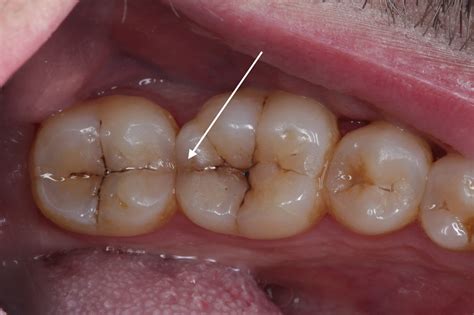

Fractured Cusp A piece of the tooth's chewing surface breaks off. Often requires a crown to restore the shape.

Cracked Tooth A crack runs from the chewing surface down toward the root. Usually needs a crown to prevent the crack from spreading.

• Dental Crowns: This is a very common solution for a crack in tooth. A crown (a cap) covers the entire tooth, providing support and preventing the crack from spreading further under the force of chewing.